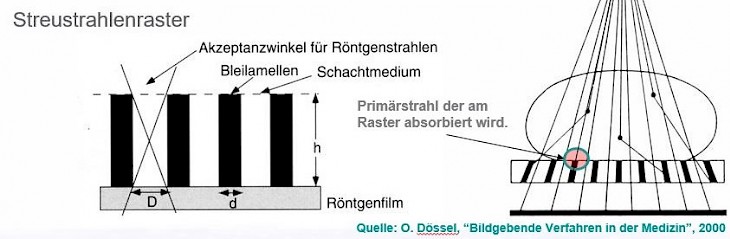

Das Raster ist wie eine Lamellenjalousie aus schmalen Streifen von stark absorbierendem Material (meist Bleifolie) und durchlässigeren Abstandhaltern (meist Spacern aus Aluminium oder Zellulose) aufgebaut.

Die Streifen stehen parallel zur Strahlung. Die erwünschte gerichtete Strahlung kann die Spacerstreifen durchdringen, Streustrahlung bleibt in den Bleistreifen hängen.

Raster bestehen aus Absorber-Lamellen der Dicke d und der Höhe h, die in regelmäßigen Abständen D nebeneinander angeordnet sind. (Siehe Abb. re)

Raster bestehen aus Absorber-Lamellen der Dicke d und der Höhe h, die in regelmäßigen Abständen D nebeneinander angeordnet sind. (Siehe Abb. re)

Zwischen den Absorber-Lamellen befindet sich ein schwach absorbierender Stoff, das Schachtmedium, das kann Papier, Kunststoff oder Aluminium sein.

Das Lamellen Material ist meist Blei kann aber auch Wolfram sein. Die Abdeckung besteht aus Aluminium oder Kohlefaser mit Kunststoff.

Durch das Streustrahlenraster gelangen im Wesentlichen nur die genau in Längsachse der Rasterschächte und somit direkt vom Fokus ankommenden Quanten. Alle anderen werden weitgehend von den Bleilamellen absorbiert.